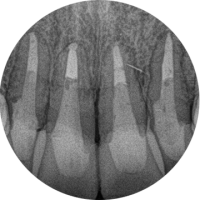

Before

左上3番の疼痛・腫れを主訴として来院

CT撮影により、歯性副鼻腔炎と診断